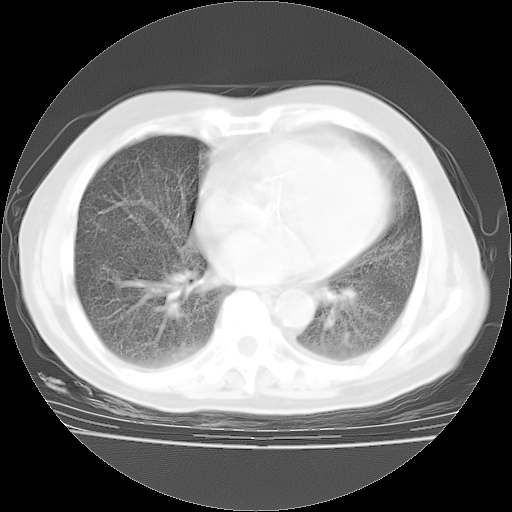

4月14日肺部CT

23.JPG

24.JPG

25.JPG

26.JPG

肺部CT平扫未见异常。